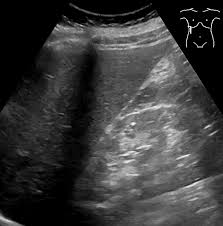

복부 초음파는 초음파(ultrasound)를 이용해 복부 내 장기들의 상태를 확인하는 비침습적 검사 방법입니다. 방사선을 사용하지 않아 인체에 해롭지 않고, 고통 없이 실시간으로 복부 장기들을 관찰할 수 있다는 점에서 가장 기본적이면서도 효과적인 진단도구로 평가받습니다.

초음파 탐촉자(Probe)에서 발생한 고주파 음파가 인체 내부 장기에 부딪혀 반사되며, 복부 초음파로 알 수 있는 것은 바로 이 반사파를 영상화해 간, 담낭, 췌장, 비장, 신장(콩팥), 방광, 대동맥, 림프절 등의 상태를 분석하게 됩니다.